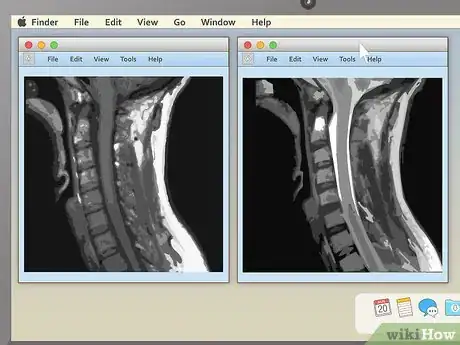

3Pick an appealing series layout. MRI programs almost always have the ability to display more than one image at once. This makes it convenient for doctors to compare different views of the same area or even MRIs taken at different times. For most non-doctors, it's easiest to simply choose a one-image-at-a-time layout and cycle through the images individually. However, there should be onscreen instructions to show two, four, or many more images at once, so feel free to play around with this feature.

2Examine the structure of the vertebrae for spinal MRIs. MRIs of the spine are typically some of the easiest for non-doctors to read (especially in sagittal view). Look for noticeable misalignments in the vertebrae or fluid discs. Having just one of either be out of alignment (as in the example above) can be the source of serious pain.

- Behind the spinal vertebrae, in sagittal view, you'll see a white, rope-like structure. This is the spinal cord, the structure connected to all the body's nerves. Look for spots where the vertebrae or discs seem to "pinch" or press into the spinal cord — because the nerves are so sensitive, just a little pressure can lead to pain.